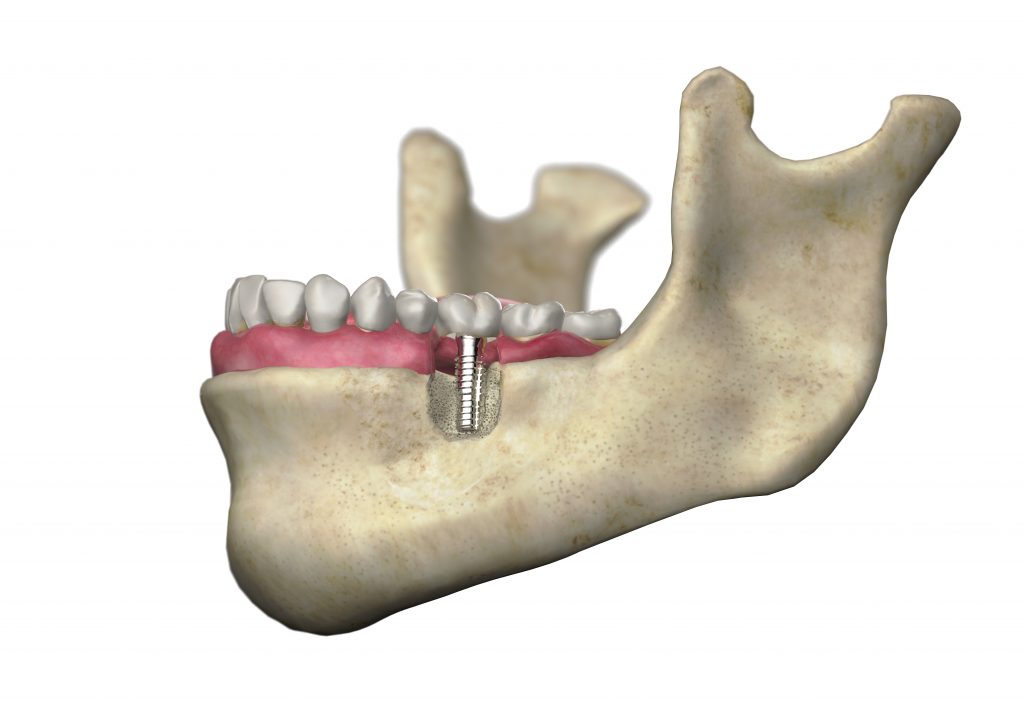

Implantes dentales modernos

Los implantes dentales modernos constan de tres partes: un pequeño poste metálico, un conector llamado pilar, y una corona o prótesis personalizada. El poste (a menudo de titanio) se inserta quirúrgicamente en el hueso maxilar, actuando como una raíz dental. En pocos meses, el hueso cicatriza alrededor del poste (proceso llamado oseointegración), fijándolo firmemente. Luego, se coloca una corona o puente personalizado. El resultado es un diente que luce, se siente y funciona como uno real.